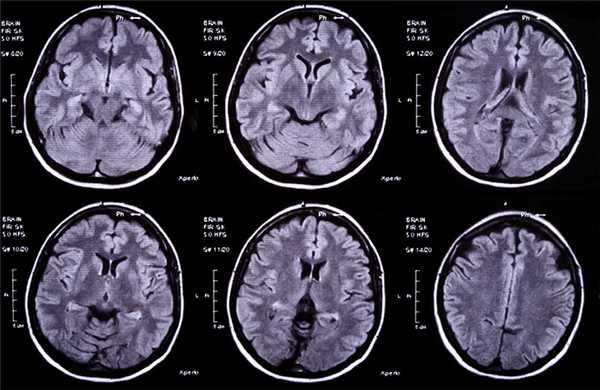

МРТ головного мозга — более точный метод диагностирования. При проведении МРТ на первых стадиях формирования абсцесса мозга (1-9 сутки) энцефалитический очаг выглядит: на Т1-взвешенных изображениях — гипоинтенсивным, на Т2-взвешенных изображениях — гиперинтенсивным. МРТ на поздней (капсулированной) стадии абсцесса головного мозга: на Т1-взвешенных изображениях абсцесс выглядит, как зона пониженного сигнала в центре и на периферии (в зоне отека), а по контуру капсулы сигнал гиперинтенсивный. На Т2-взвешенных изображениях центр абсцесса изо- или гипоинтенсивный, в периферической зоне (зоне отека) гиперинтенсивный. Контур капсулы четко очерчен.

Для того чтобы провести точную диагностику места расположения абсцесса мозга и мозжечка, проводят компьютерную и магнитно-резонансную томографию головного мозга. При проведении компьютерной томографии выявляется тонкая, гладкая стенка абсцесса, которая имеет правильные контуры. Магнитно-резонансная томография позволяет также определить капсулу абсцесса. Если нет возможности провести вышеперечисленные виды исследования, можно провести пневмоэнцефалографию или радиоизотопную сцинтиграфию головного мозга.